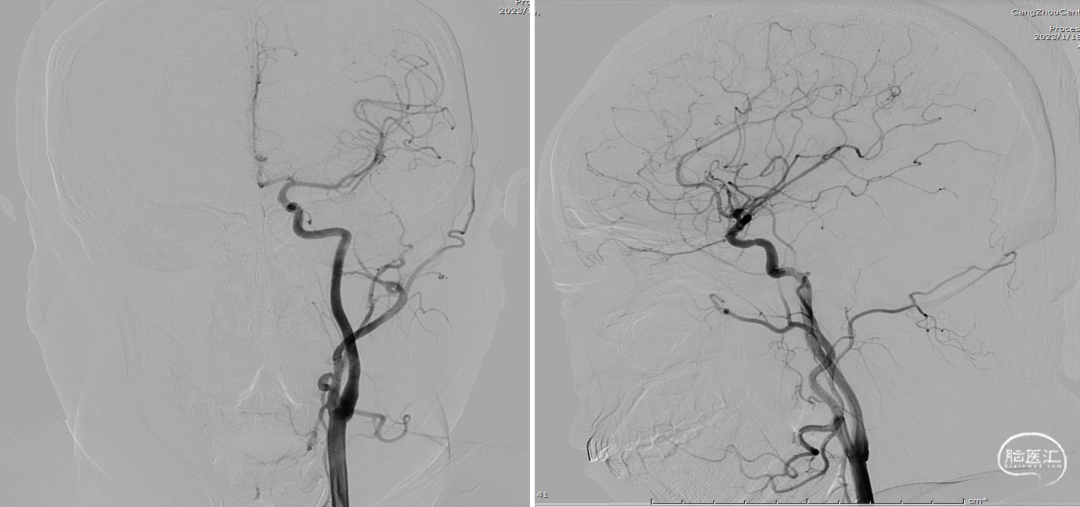

术前造影

全脑血管造影(2022-07-22)

左颈内动脉3D重建图像(4.6mm*4.9mm)

半年后全脑血管造影复查(2023-01-18)

半年后全脑血管造影复查-3D重建(2023-01-18)

半年后全脑血管造影复查-3D重建及透视(2023-01-18)